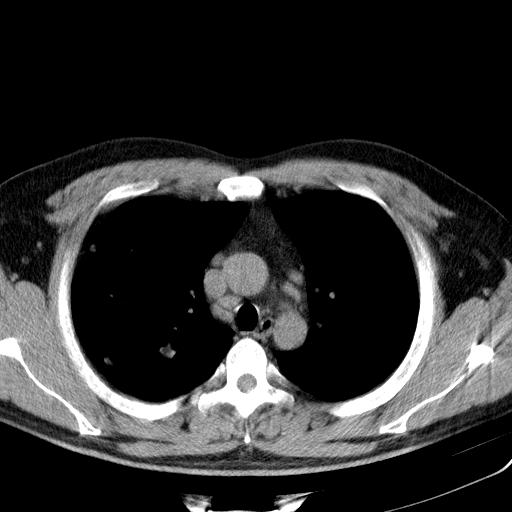

双肺散在多发类圆形结节灶,边缘较光滑,纵隔淋巴结肿大,考虑转移瘤

淋巴结近呈对称性肿大,肺部多发结节,首先考虑结节病,其次考虑转移瘤。

双肺及胸膜下见多发结节影,最大直径约0.4,内密度均匀,中纵隔腔静脉后见小淋巴结影。

首先考虑转移瘤,建议查原发灶;

炎性疾病待排